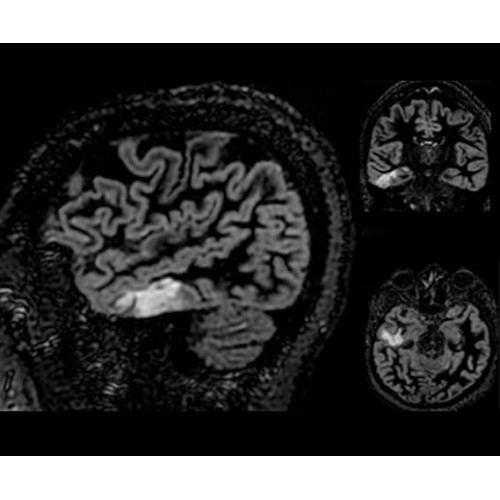

• Специальный пакет приложений для измерения и сравнения объемных изображений ЦНС с нормами поможет вам в диагностике нейродегенеративных заболеваний, а дополнительные инструменты визуализации — в постановке точного диагноза с помощью бета-амилоидов и радиоизотопных маркеров ФДГ.